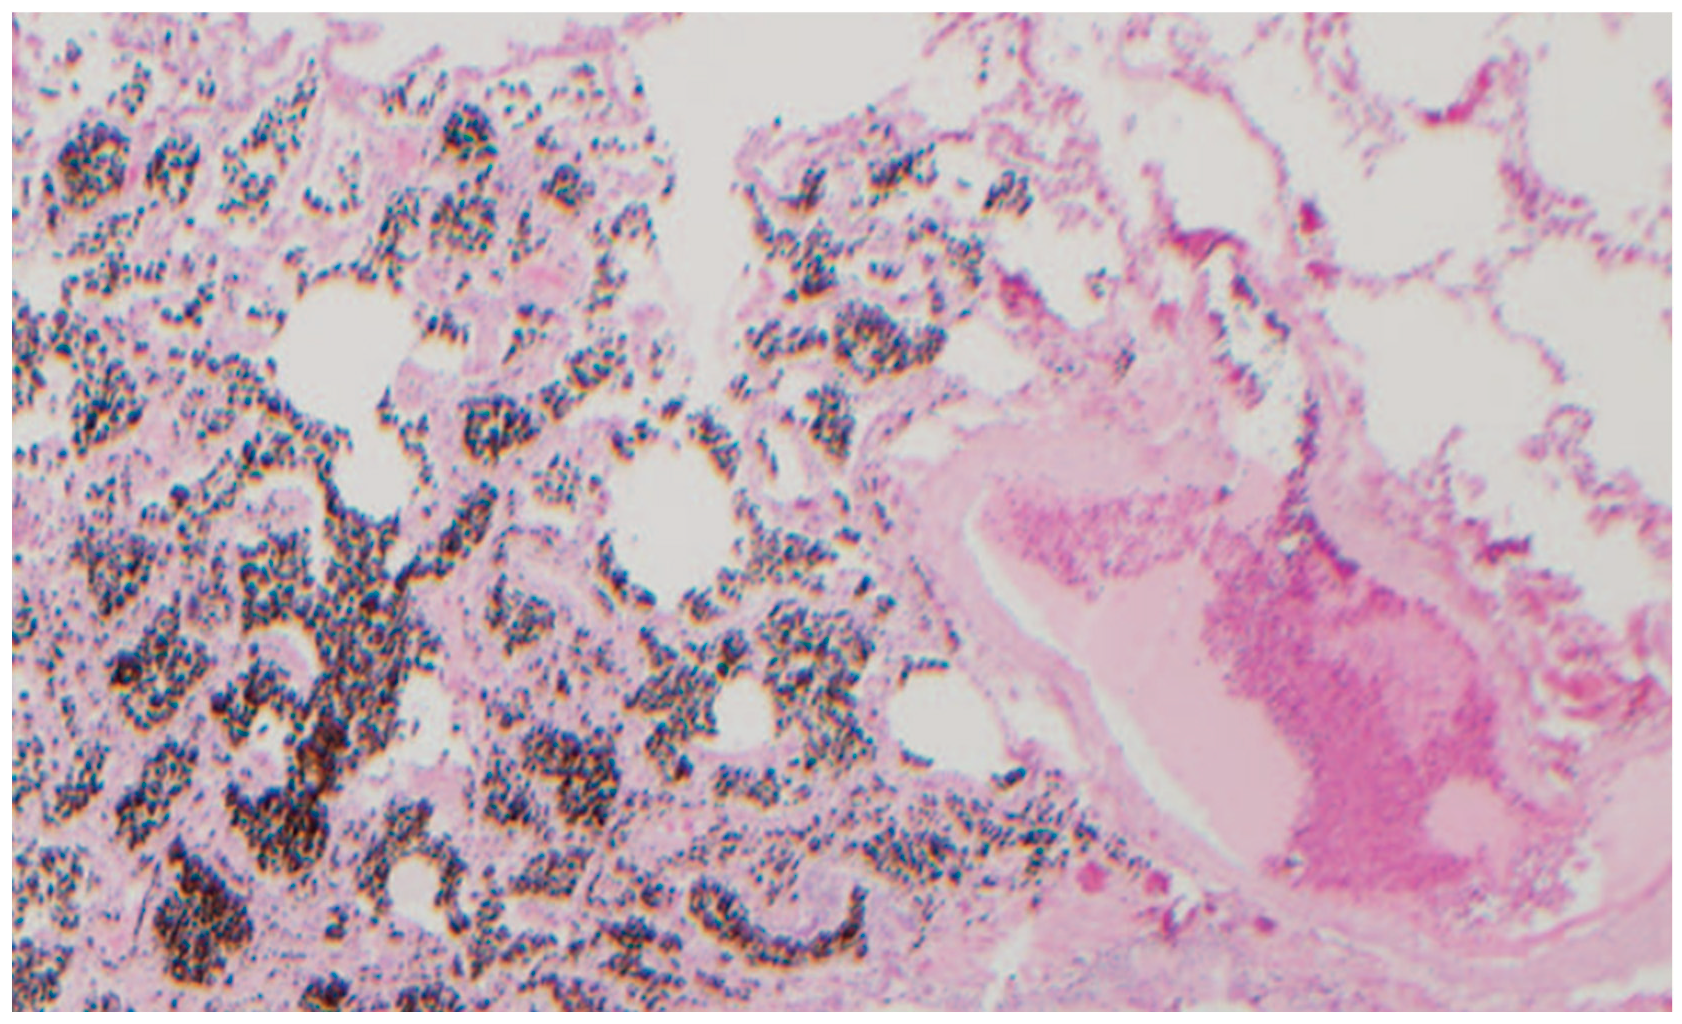

3.1.1. Case 1

3.1.2. Case 2